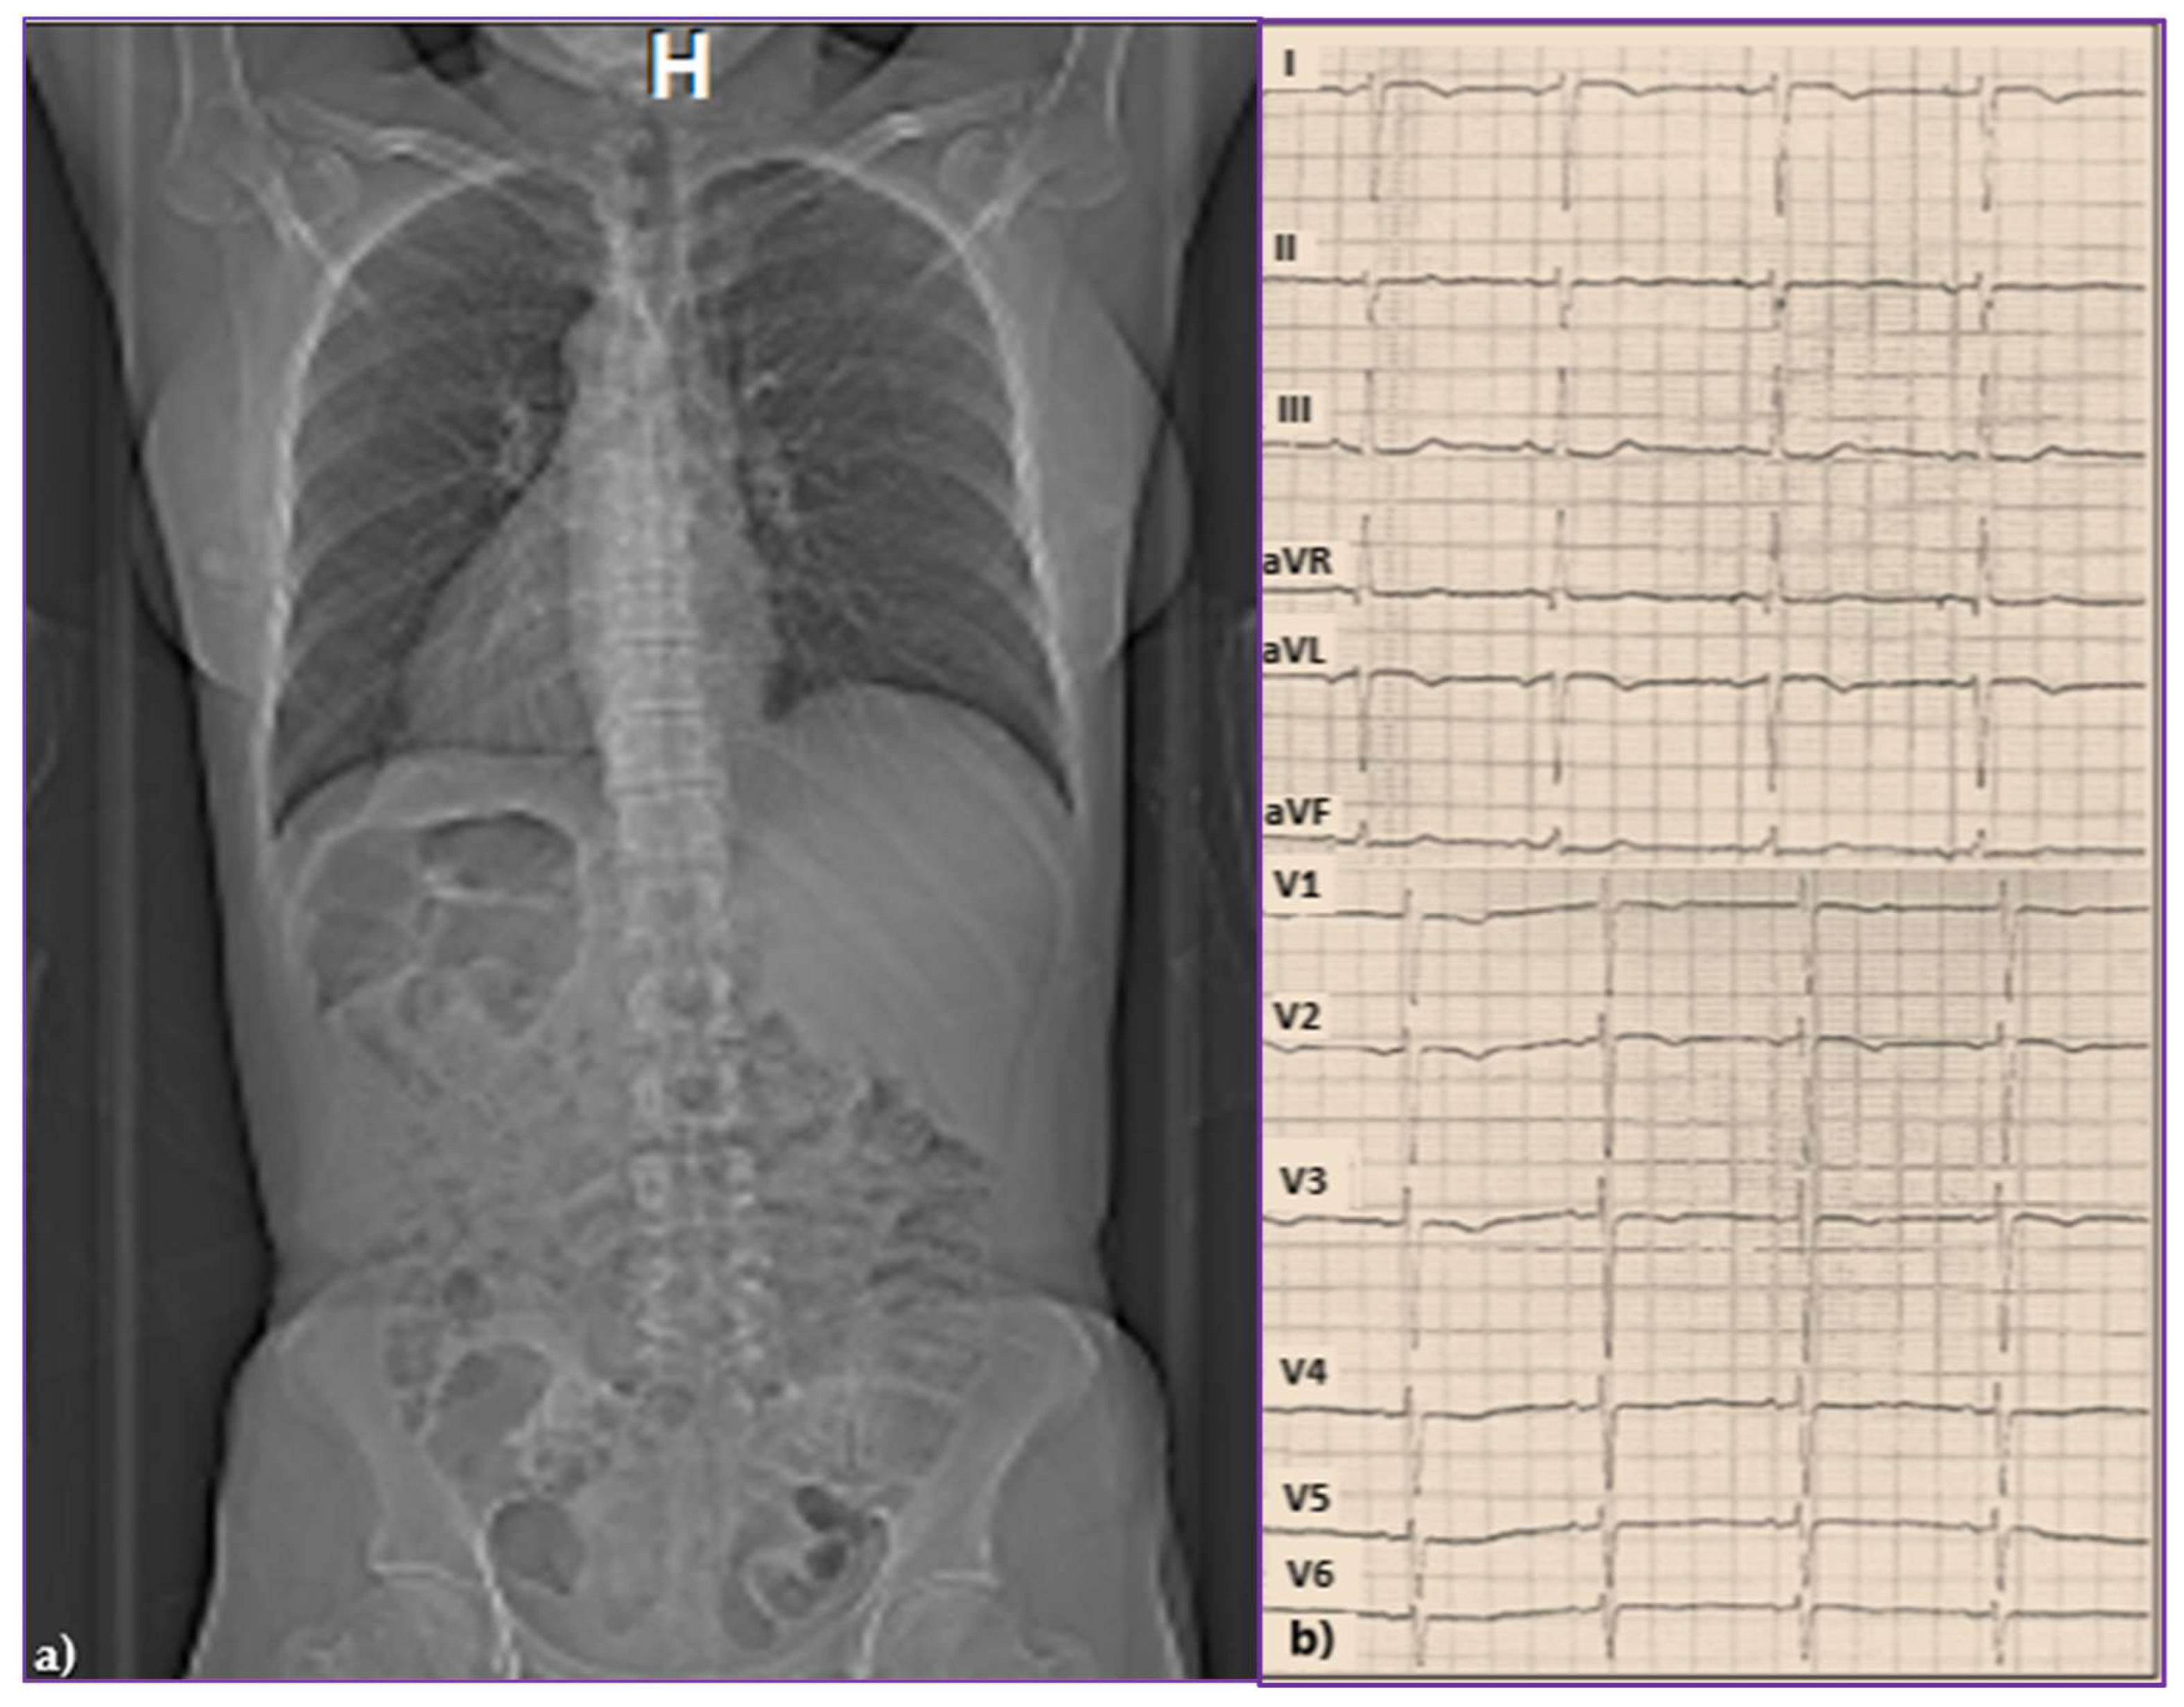

2.1. Initial Presentation

2.2. Diagnostic of SSS and Pacemaker Implantation